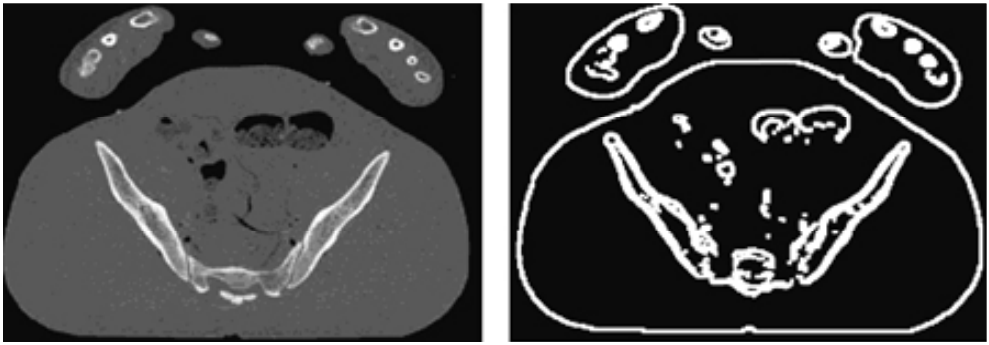

- 아래 그림의 실험에서 사용된 CT 슬라이스 이미지이다. 각각 587 X 341 픽셀이다.

- 그 후 Canny edge detector를 사용하여 edge를 추출한다. (아래 그림 참고) Canny edge detector는 스케일 위치를 계산할 때 적합한 시작점이다.